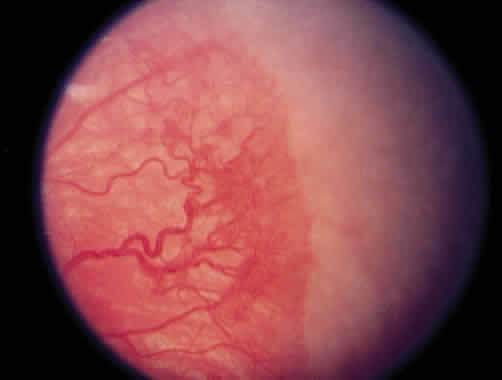

The most common form of regression of ROP is continued growth of the retinal vasculature anteriorly with gradual fading of the disease at the border of posterior vascularized and anterior avascular retina. Another more dramatic sign of regression is the growth of vessels beyond the ridge (Fig. 1). The vessels penetrate into the avascular retina as an arteriole with an accompanying venule. As the vessels grow beyond the ridge, the dilation and tortuosity of vessels just posterior to the shunt and in the posterior pole diminish.

Fig. 1. Regressing retinopathy of prematurity. The vessels have crossed the ridge and are growing into the avascular zone.